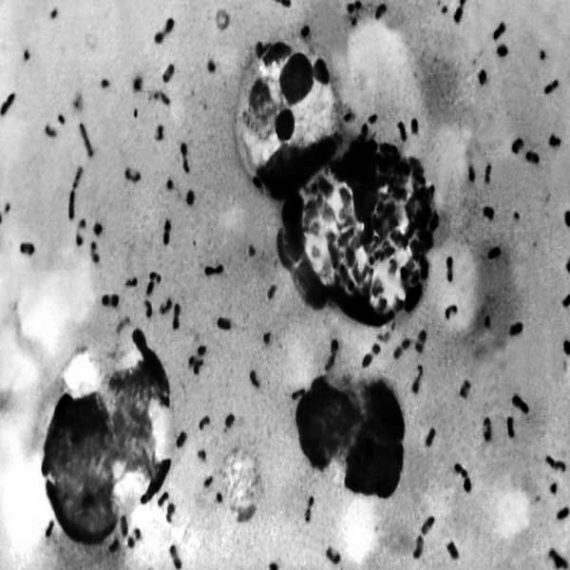

Sadistik où comment surfer sur le tsunami pandémique mondial du covid-19 sans le faire exprès ou sans en avoir l’air, chacun se fera son avis. The Plague son nouveau single…